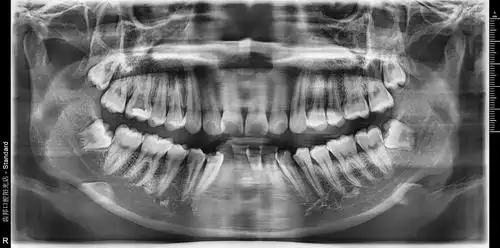

可以帮忙看看我的牙片吗